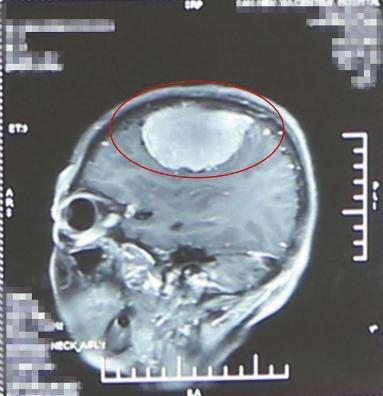

在她大脑硬膜与脑组织间有一个肿瘤,直径7厘米,足有成人拳头大!需要赶紧切除!

到了医院后,经头颅CT和磁共振一系列相关检查,显示在张大娘的硬脑膜与脑组织间有一个7厘米的肿瘤,足有成人拳头大,已压迫到运动前区。难怪张大娘的右胳膊和右腿不听使唤了。

可如果手术,张大娘的巨大脑瘤已从额叶左侧向中心扩张,侵犯到上矢状窦。而上矢状窦是大脑上方的一根大静脉,汇集了大脑回流的血液。如果手术切除肿瘤过程中伤及矢状窦,会引起颅内大出血,张大娘很可能下不了手术台。

他俩发现,张大娘的脑瘤起源于硬脑膜,侵犯了颅骨内板,侵犯面积大,血供丰富。

两人配合默契,切除脑瘤的同时保护上矢状窦,保护静脉回流。

由于肿瘤侵犯硬脑膜面积大,切除后硬脑膜缺损大,还要进行硬脑膜成型术,就是用生物材料补片代替和修补缺损的硬脑膜。

为给张大娘省钱,卢国奇决定用张大娘自体的颞肌筋膜为她修补硬脑膜,而不用昂贵的生物材料补片。这样做,虽然给手术团队增加了难度,但能为经济拮据的张大娘省下1万多块,手术效果也不受影响,卢国奇“心里别提多高兴了”。

经过奋战,巨大脑瘤成功切除,考虑到肿瘤细胞源发于硬脑膜,还侵犯到颅骨内板,为防止肿瘤细胞残存在颅骨内板,形成新的病灶,卢国奇又用磨钻磨除了一部分颅骨内板,以绝后患。